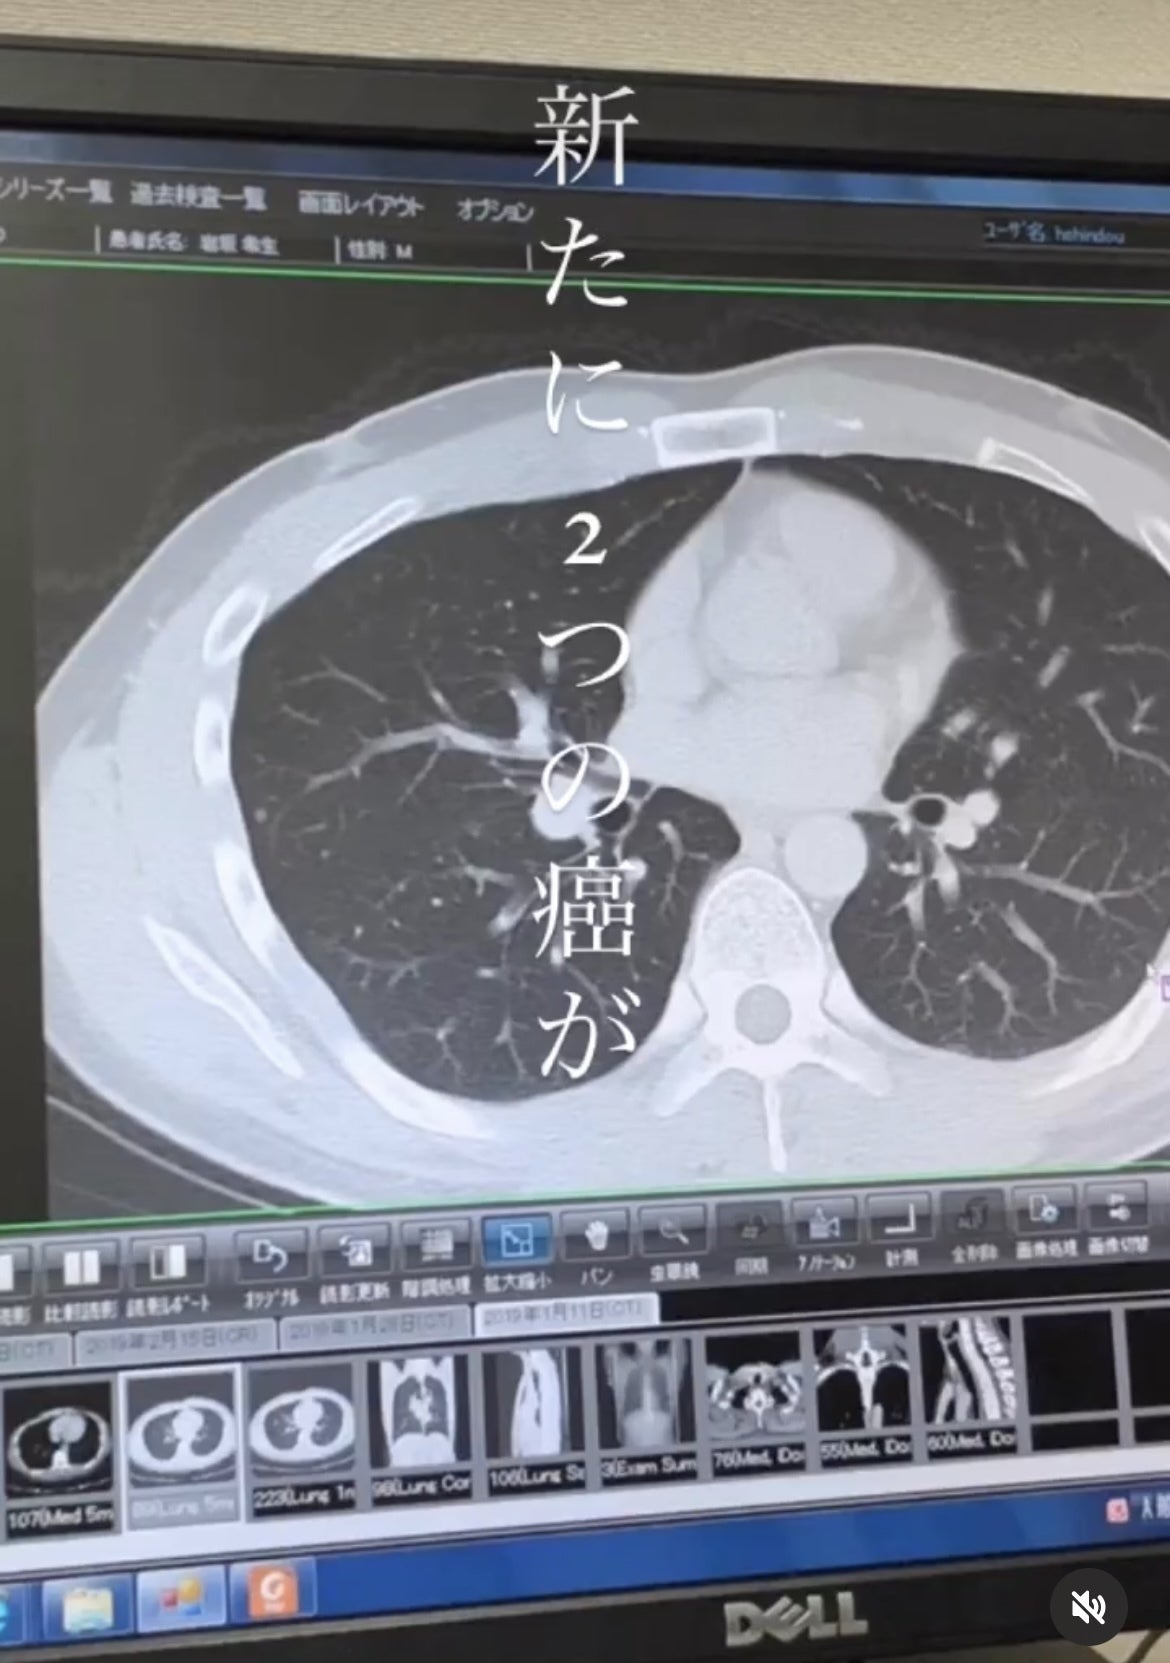

16歳で膝に癌が見つかる

滑膜肉腫(かつまくにくしゅ)という希少ガンでした。

25歳で甲状腺乳頭癌と肺癌が見つかり、

甲状腺を全摘しました。

現在も定期的に放射線治療を受けながら闘病中です。

これまで3つの癌と戦ってきたからこそできる、